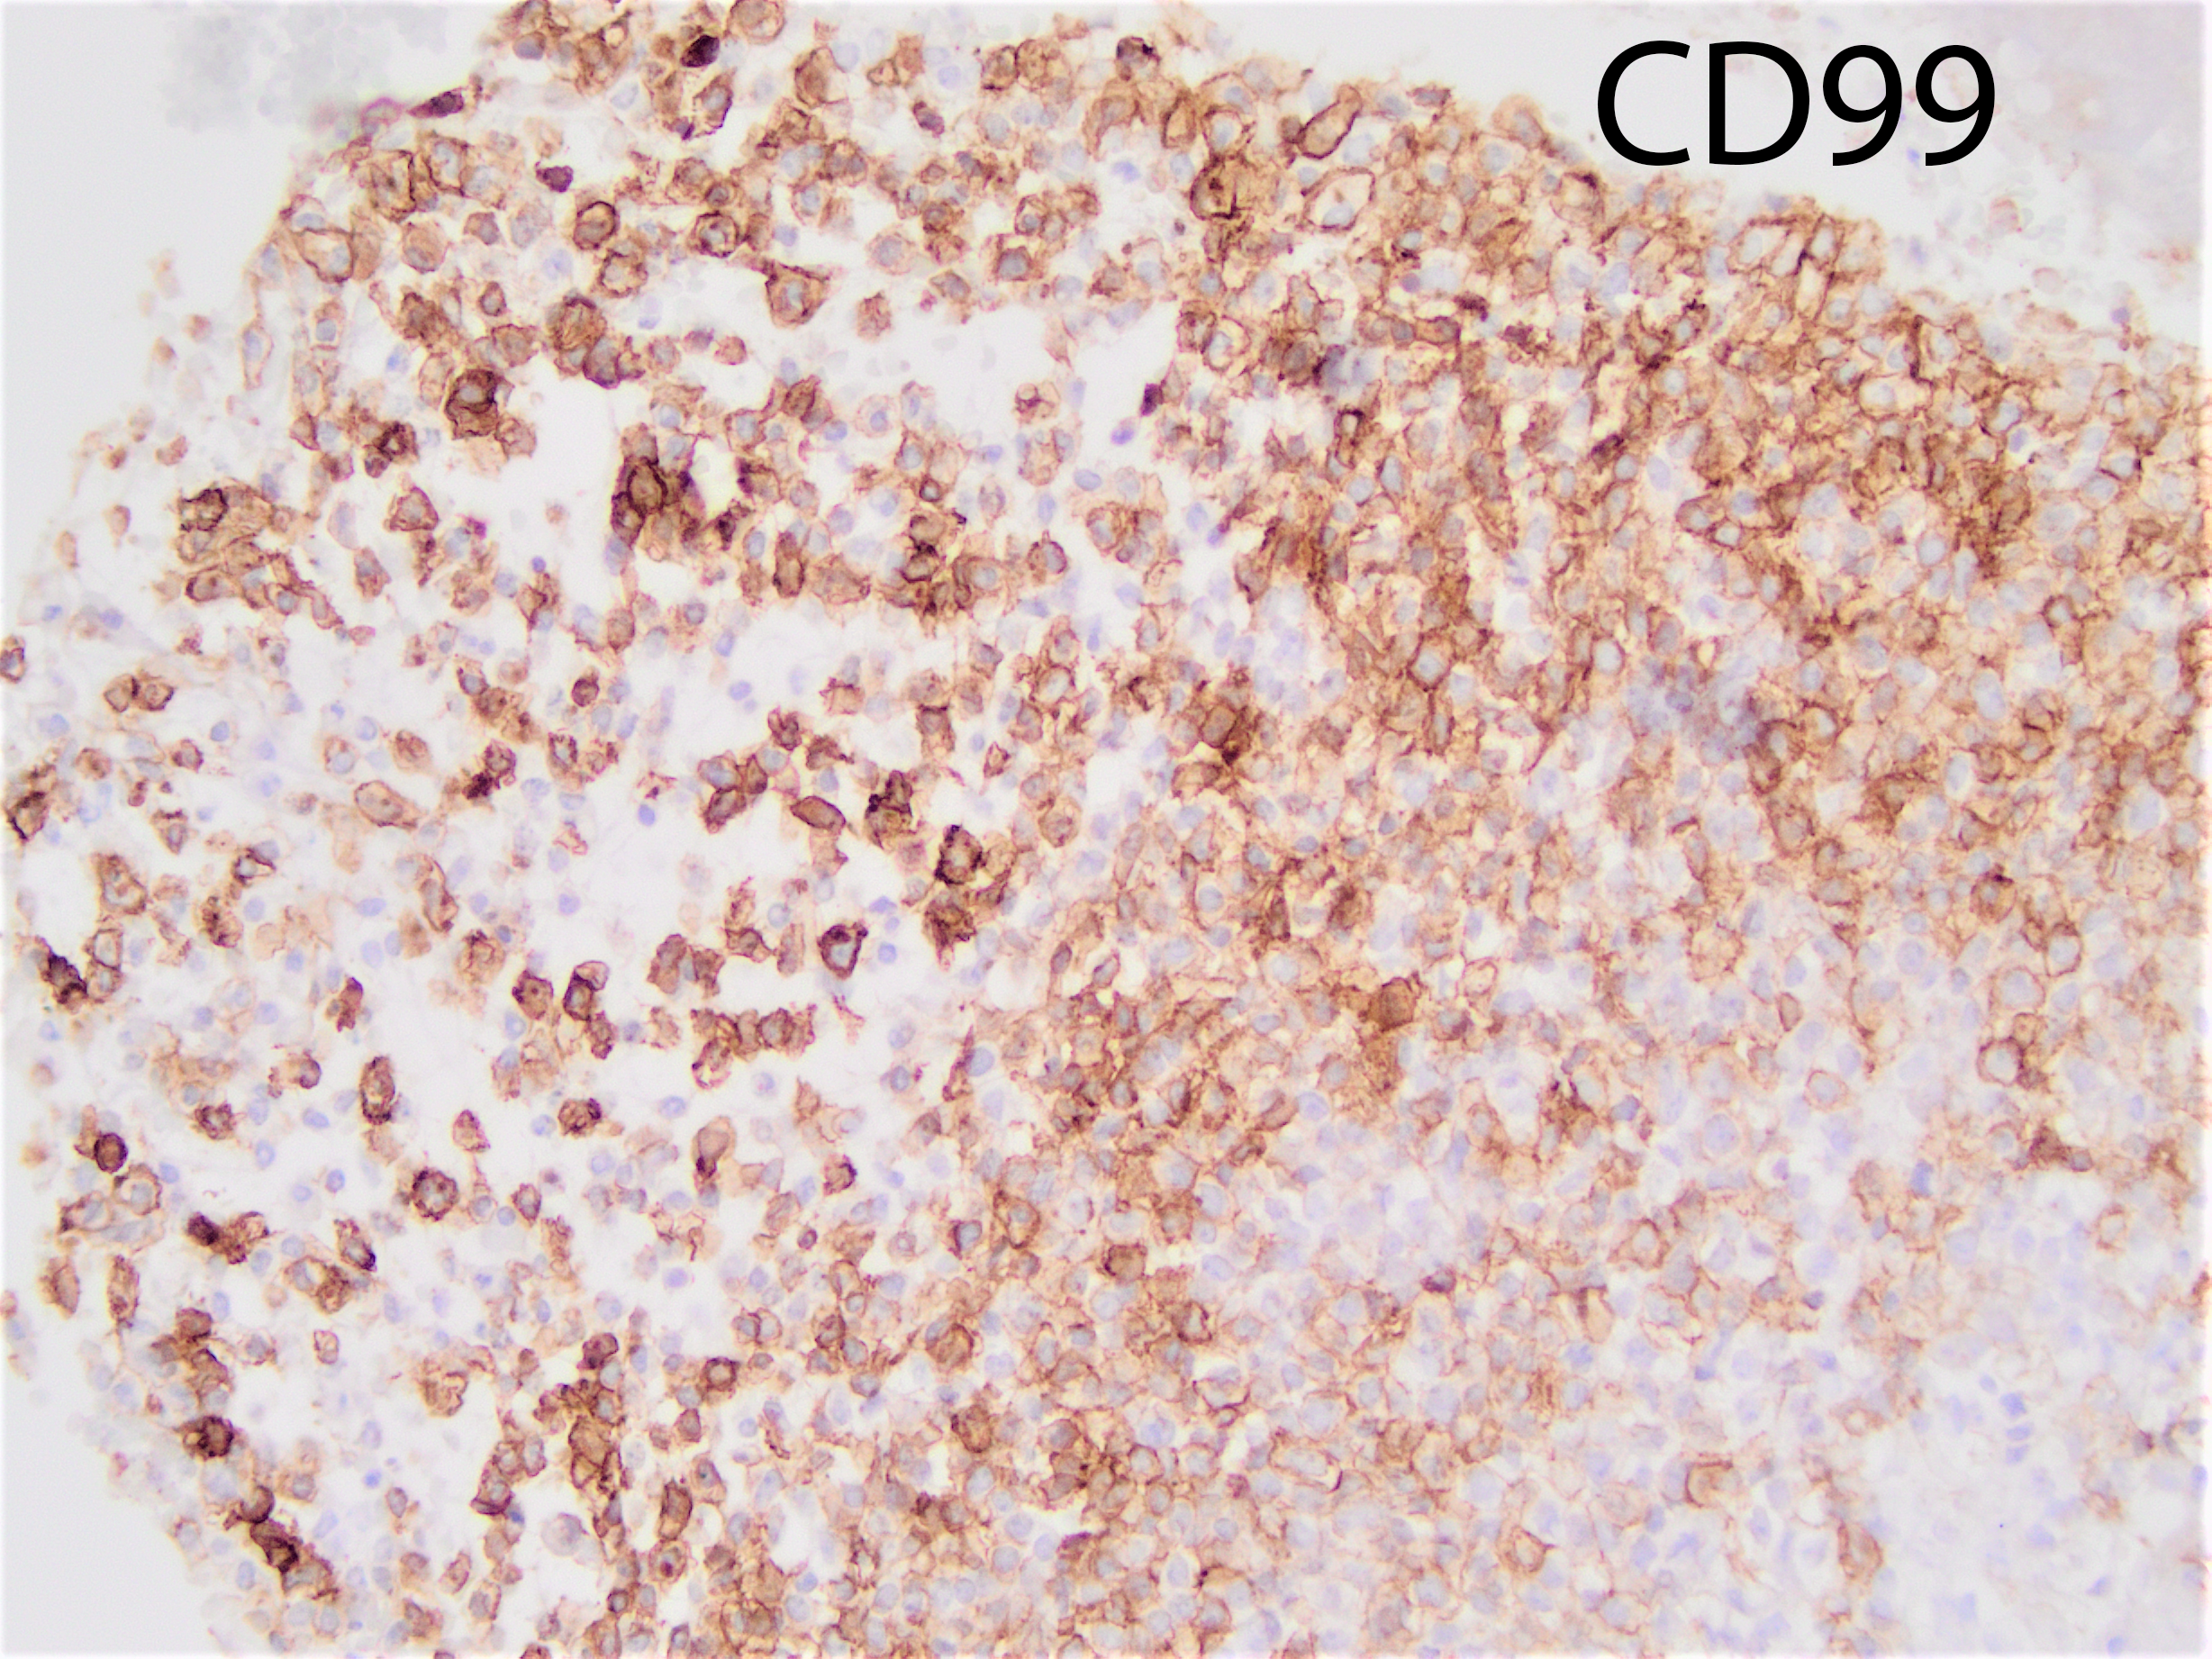

The tumor shows strong cytoplasmic positivity for CD99. The tumor cells are negative for chromogranin, synaptophysin, CK7, CK20, pan-CK, GATA3, HMB45, PAX8, TTF1, p40, and SOX10:

CIC-DUX4 rearranged sarcoma is a small blue round cell tumor resembling Ewing sarcoma. In addition to small blue round cells morphology, CIC rearranged sarcoma may also show focal areas of spindling and epithelioid/rhabdoid phenotype, with frequent myxoid stromal changes. Similar to Ewing sarcoma, it also shows strong cytoplasmic and membranous positivity of CD99. Patient age at presentation ranges from 6 to 70 years (mean age: 32 years). Most of the time it arises in the soft tissue of the trunk and extremities. Overall survival is worse than Ewing sacrcoma.